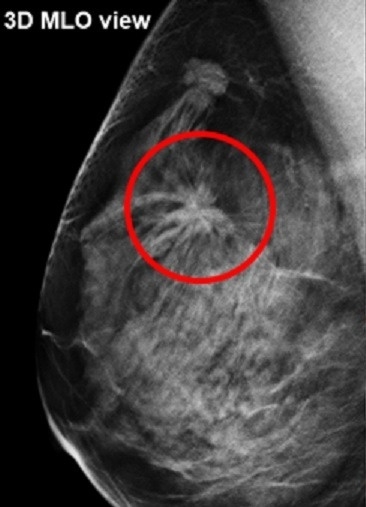

トモシンセシス(3Dマンモグラフィ)とは

通常のマンモグラフィでは、乳腺と病変部位が重なってしまい、判別しにくいことがあります。しかし、トモシンセシス撮影を用いることで、乳腺の重なりで見えにくかった病変を判別しやすくなり、検査精度の向上が期待できます。

検査例

3Dマンモグラフィ画像

赤丸の腫瘤影部分に悪性を疑う周辺組織を引き込む陰影を確認

資料提供:GEヘルスケア